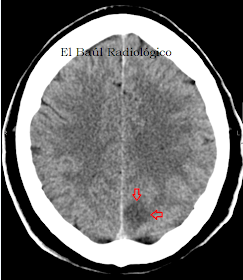

FIGURA 2) Pequeña área hipodensa (flechas) que representa un infarto isquémico subagudo en el lóbulo temporal izquierdo.